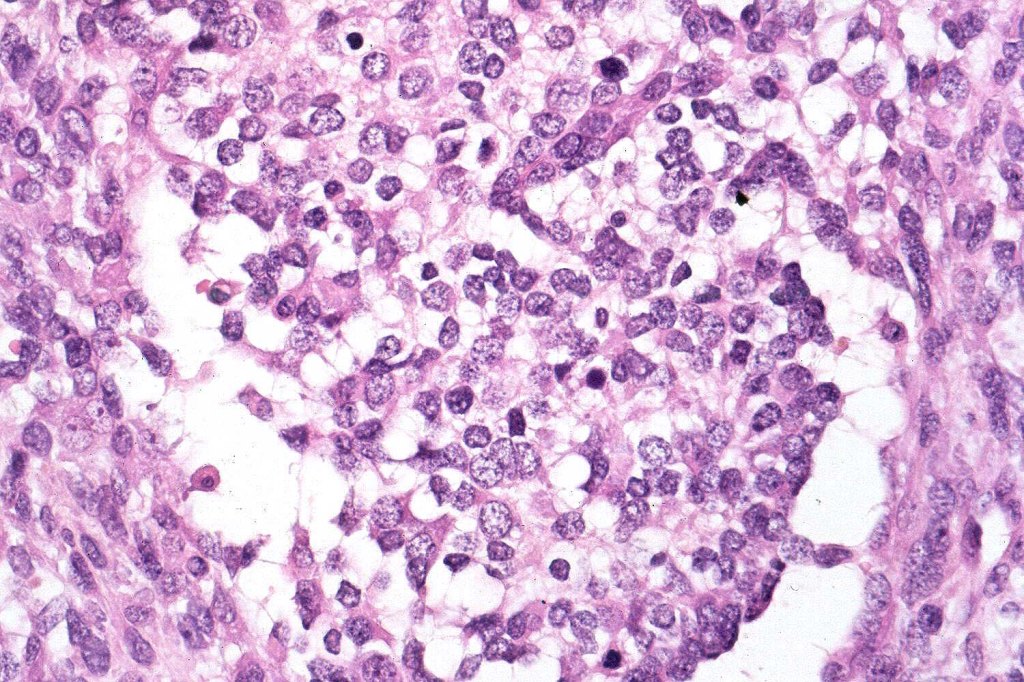

•Ganglioneuroblastic

•Neuroendocrine